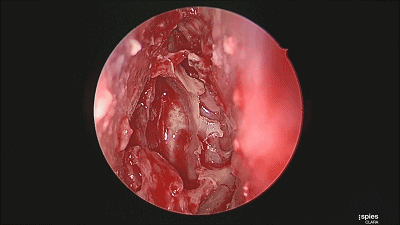

▼切开黏软骨膜后始可开始分离。若剥离子在黏膜与软骨膜之间,软骨膜仍盖于软骨上,则呈柔软红色;若软骨膜已分开,则呈闪光白色的表面。

![]()

▼用鼻中隔剥离子分离切口侧鼻中隔软骨膜及骨膜,弯曲面向软骨及筛骨垂直板分离时自上而下并与鼻梁平行分离黏软骨膜直至犁骨,此部位软骨膜常有粘连愈着,分离时应用宽钝器械,不要用小而锐的器械,以避免穿孔。